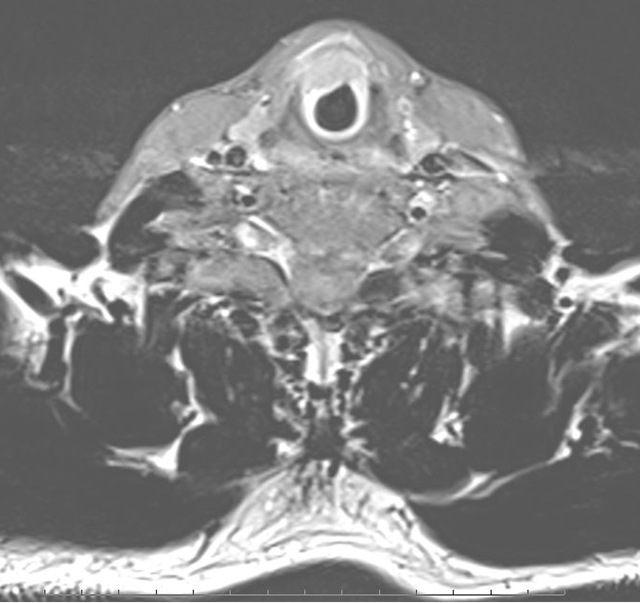

增强MRI可见肿瘤侵犯环状软骨

泸州患者老张声音嘶哑2个多月,一查——喉癌。电子喉镜下肿瘤呈贯声门型,增强MRI显示已侵犯环状软骨。